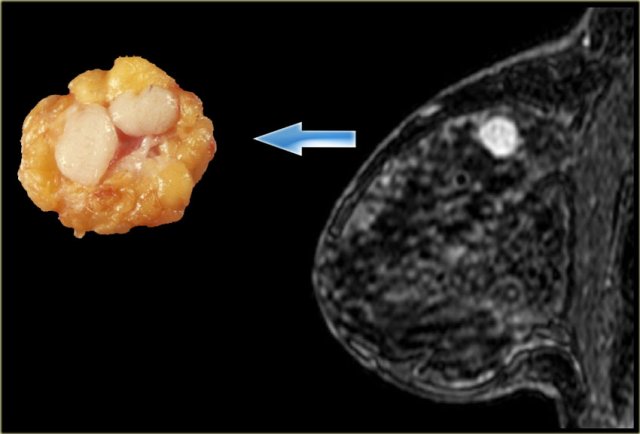

Margins can be described as smooth, irregular, or spiculated .

Spiculated margins are frequently a feature of malignant breast lesions and radial

scars.

If a mass has spiculated margins, it has an 80% chance of being malignant.

The image on the far left shows a spiculated mass, i.e. 80% chance of being malignant. .

Next to it the corresponding gross pathologic specimen.

You can see the spiculations invading the surrounding tissue in both.

Just like on mammography, this lesion is has a high likelihood of malignancy and would be labelled BIRADS 5.